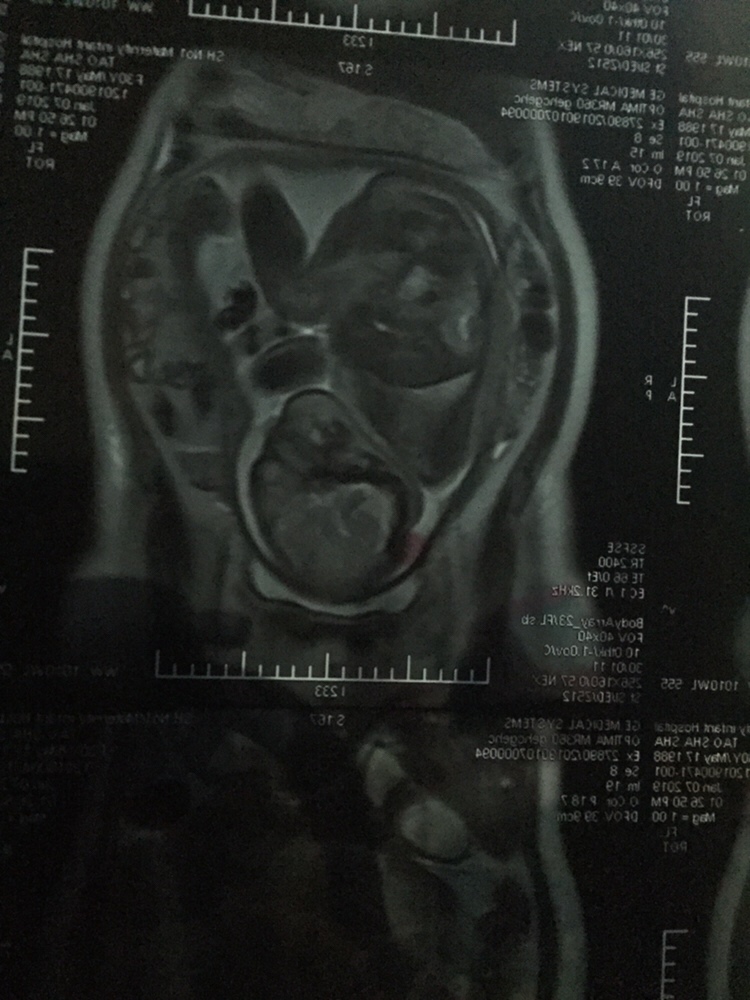

怀孕可以拍核磁共振?没有辐射吗

孕31周+3天

难道你拍的核磁?感觉入盆啦……头位,挺好的。

桃子[帖主]:是的,拍了核磁共振,排除胎盘植入

第一次看到这种B超图,长见识了